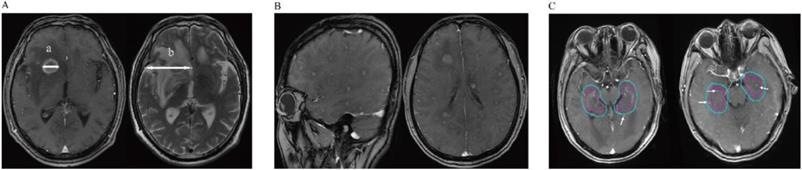

MRI is routinely used at our center to diagnose BM. All scanning was performed using the same 1.5 T MRI machine (GE Healthcare, Waukesha, WI). MRI studies included pre- and post-Gd administration sequences. The images obtained before administering contrast agent were axial T1- and T2-weighted images (6-mm sections, 1-mm gap), and sagittal T1-weighted images (4-mm sections, contiguous). The images obtained after administering contrast agent were axial and coronal thin-section images (4-mm, contiguous), and T1-weighted images (fast spoiled gradient-recalled echo acquisition [FSPGR]; repetition time: 120-215; echo time: 2.2-2.8). For each patient, brain MRI scans were reviewed by two experienced radiologists, and three variables reflecting radiological features were measured: 1) BM number; 2) BM size on T1-weighted Gd-enhanced imaging; and 3) peritumoral brain edema size (PBES) on T2-weighted imaging. For patients with multiple brain tumors, the largest lesion was accurately measured in one dimension (the longest diameter along the plane of measurement), and this value was used for analysis [7]. PBES was calculated by subtracting the diameter measured on T1-weighted Gd-enhanced imaging from the diameter on T2. If no peritumoral brain edema (PBE) was observed, the edema size was evaluated as zero. As shown in Figure 1A and reported previously, PBES was found to be vasogenic edema, and was associated with tumor size [8-10]. Therefore, we subsequently refer to the “vasogenic edema ratio” as previously reported by Tung et al. [11]. To minimize the effect of tumor size on PBES, we defined the relationship between the tumor and its associated PBES as the peritumoral brain edema index (PBEI), calculated by dividing PBES by tumor size. Thus, for PBES and PBEI, the larger the value, the greater the degree of PBE present. Hippocampal or peri-hippocampal metastases were defined as metastatic lesions in the region of the hippocampus and within a 5-mm margin (hippocampus and peri-hippocampus (PH) region), evaluated by enhanced MRI as described previously for the RTOG 0933 trial [12].

A: Detailed method of evaluating metastatic brain tumors; The maximum diameter (a) of the tumor (TS) was measured in T1-weighted Gd-enhanced image. Then we also measured the maximum diameter of its associated peritumoral brain edema (PTBE) (b) at the same slice of the T2-weighted image. The “peritumoral brain edema index” (PBEI) was defined as (b-a)/a. B: T1-weighted Gd-enhanced image demonstrates the patient with diffuse brain metastases. C: Two patients with hippocampus and Peri-Hippocampus region metastases in SBM group. The red circle means the hippocampus area, the blue circle means the Peri-Hippocampus region.

The radiological features of patients are summarized in Table 2. In total, 13 and 27 BM patients in the MBM and SBM groups, respectively. A higher proportion of patients in the MBM group had ≤3 BM. 3 patients had >3 BM (8, 4, 4), the lesions were stable or decreasing after chemotherapy (2 patients) or target therapy (1 patient) without local BM treatment, meaning that the patients were more suitable for stereotactic radiation therapy according to current guidelines [14]. Only one patient (in the SBM group) showed a diffuse BM pattern as described elsewhere (Figure 1B). Additionally, we found that patients in the MBM group had more favorable results for radiological features including BM size, PBES, and PBEI than those in the SBM group, suggesting that patients in the SBM group had more aggressive metastatic disease. In our cohort, only two patients (5.0%) had metastases in the hippocampus and peri-hippocampus region, and both were in the SBM group (Table 2 and Figure 1C).